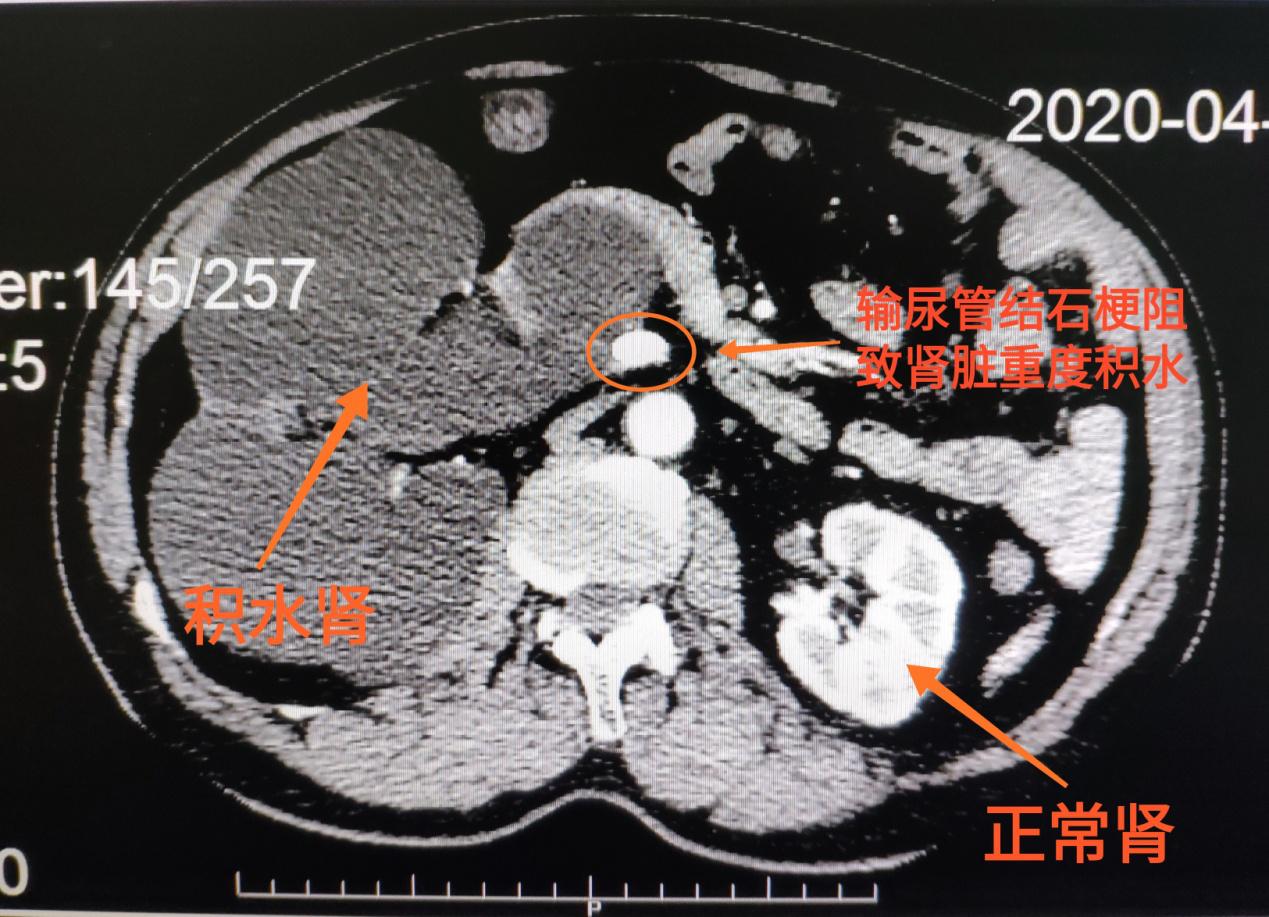

57岁的曾先生平素身体健康,在例行体检时,B超发现右肾重度积水,当地医院建议他做进一步的检查治疗。曾先生来到长沙市第三医院,泌尿外科主任罗飏为他完善CT等相关检查,只见右侧输尿管上段赫然一颗长1.5cm(约枣核大小)结石。

这颗结石堵住了右侧输尿管,造成同侧肾脏重度积水,肿胀成了一个大“水袋”。如果不尽快手术解除输尿管梗阻,不能及时排出的尿液可能引起细菌繁殖,引发肾内感染、肾积脓、甚至尿源性脓毒血症等严重并发症;而肿大的积水肾不仅几乎完全丧失功能,还会挤压附近的血管、肠道等脏器,影响器官功能。